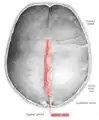

Sagittal suture

The sagittal suture, also known as the interparietal suture and the sutura interparietalis, is a dense, fibrous connective tissue joint between the two parietal bones of the skull. The term is derived from the Latin word sagitta, meaning arrow.

The sagittal suture is formed from the fibrous connective tissue joint between the two parietal bones of the skull.[1] It has a varied and irregular shape which arises during development.[1] The pattern is different between the inside and the outside.[1]

Two anatomical landmarks are found on the sagittal suture: the bregma, and the vertex of the skull. The bregma is formed by the intersection of the sagittal and coronal sutures. The vertex is the highest point on the skull and is often near the midpoint of the sagittal suture.

Animation. Sagittal suture shown in red.